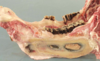

Gangrenous pericarditis (complication of traumatic reticuloperitonitis)